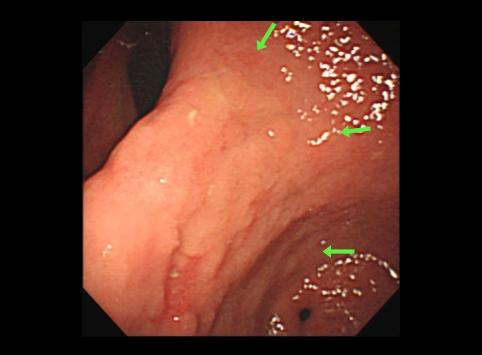

clasificación del pacienteTumor Epitelial Maligno/Adenocarcinoma

parte(separada por órganos)estómago(región)/mas de dos

método de exámenEndoscopia

clasificación ectoscópica de tumoresTipo 0(tipo superficial)/Tipo IIc(IIc+IIb)

diámetro mayor del tumor40 -

grado de penetraciónm